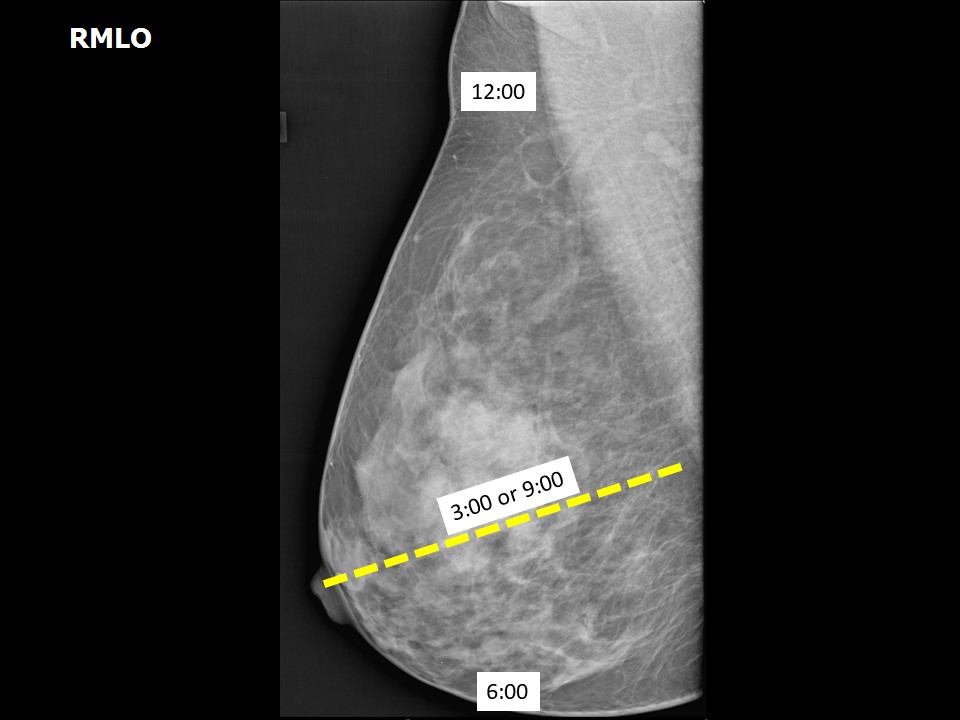

Basics

of

Interpreting

Mammogams